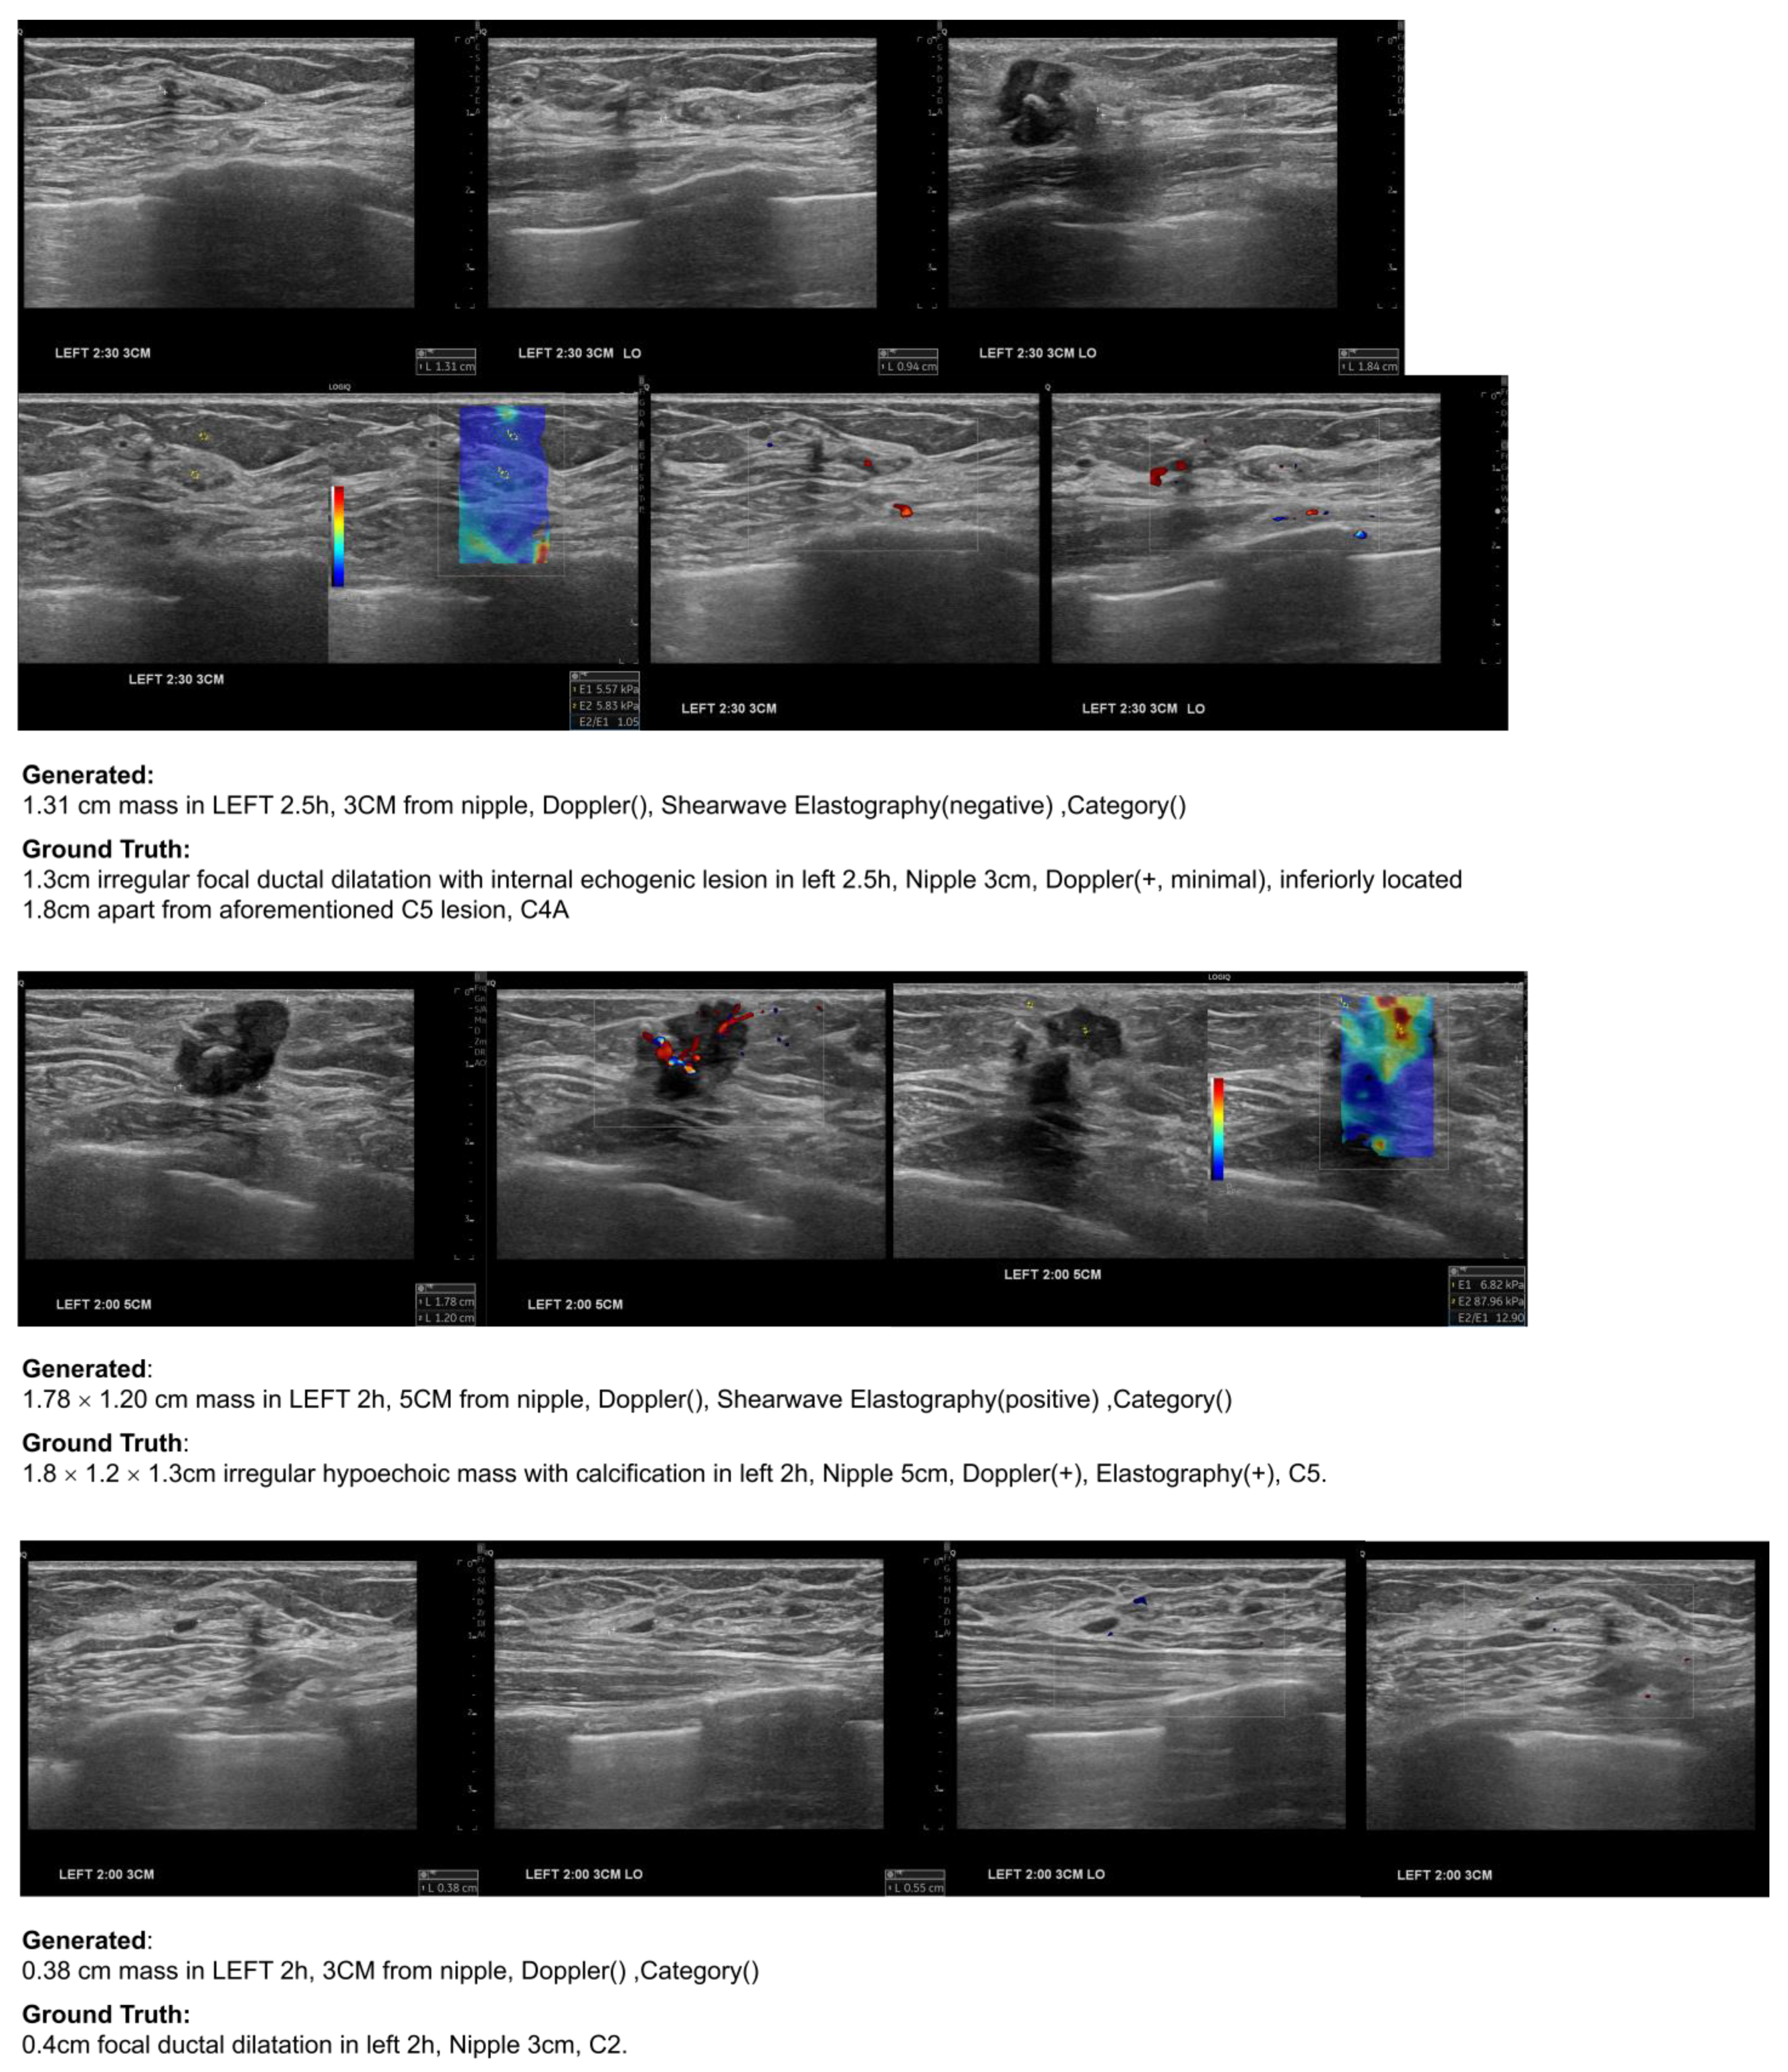

Figure 9 shows examples of automatically generated reports for individual groups of US scan images of a patient in the test dataset. The input used for these results consists of a total of 38 US scan images, with specific annotations for suspicious masses made at five out of the seven total locations. For each group, generated reports accurately captured the size and location of masses. Elastography findings were consistently identified.

Figure 9. Example of report generation on breast US images of a patient in the test dataset. Each row corresponds to a group with manual annotations, the generated report sentence, and the ground truth report sentence.